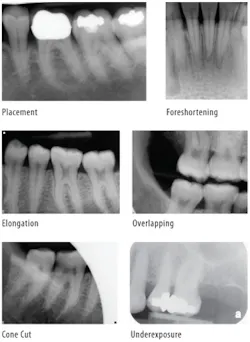

When the principles of radiographic technique are not applied, technical errors will occur. Errors need to be identified, understood, and corrected so that they do not continue to occur. The most typical technique errors occur in placement, vertical angulation, horizontal angulation, x-ray beam centering, and exposure.

Placement errors occur when the clinician fails to properly place the receptor to record the correct teeth, or cuts off the crowns or apices of teeth.

Vertical angulation errors distort the length of the structures and result in either foreshortening or elongation. Foreshortening requires a decrease in the vertical angle for correction; elongation requires an increase in the vertical angle. Vertical angulation errors are more common with the bisecting angle technique than with the paralleling technique. However, vertical angulation errors, especially elongation, can occur with the paralleling technique when the patient bites too forcefully and torques or flexes the receptor out of the correct vertical position. To correct, ensure light biting pressure with the use of a cotton roll under the biteblock, and use lingual placement away from the teeth with receptor, teeth, and PID all parallel to each other.

Horizontal angulation errors result in overlapping of proximal surfaces and limit caries and bone loss evaluations. To correct, the horizontal angle must be directed through the proximal surfaces of the teeth. It is helpful to align the lateral sides of the biteblock parallel with the teeth contacts to better guide the x-rays through the proximal contacts of the teeth. Overlapping occurs more commonly with tab bitewings. However, overlapping can occur with bitewing instruments if the receptor is not placed parallel to the horizontal plane of the teeth.

Cone cut errors are caused by not centering the x-ray beam over the receptor. Lack of centering produces partial exposure of the receptor with a "cut" where x-rays did not interact with the receptor. Receptor instruments with beam guides facilitate beam centering over the receptor when properly assembled.

Exposure errors result in light or dark images due to improper exposure time or lack of consideration of patient size and the thickness of structures. Underexposures cannot be corrected with software enhancements, but overexposures can usually be adjusted to moderate image density.